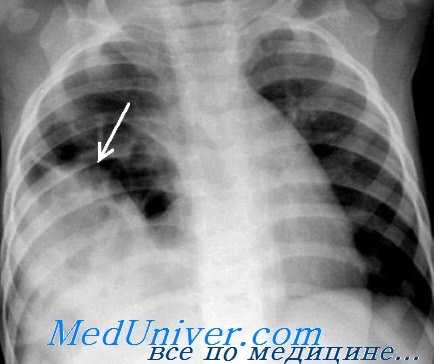

(Слева) На рентгенограмме грудной клетки у подростка, пострадавшего в ДТП, определяется пневмоторакс, плевральный дренаж и назогастральный зонд в виде извитой тени в проекции грудной клетки.

На рентгенограмме видна релаксация правого купола диафрагмы со смещением печени, что говорит о возможности повреждения самой диафрагмы